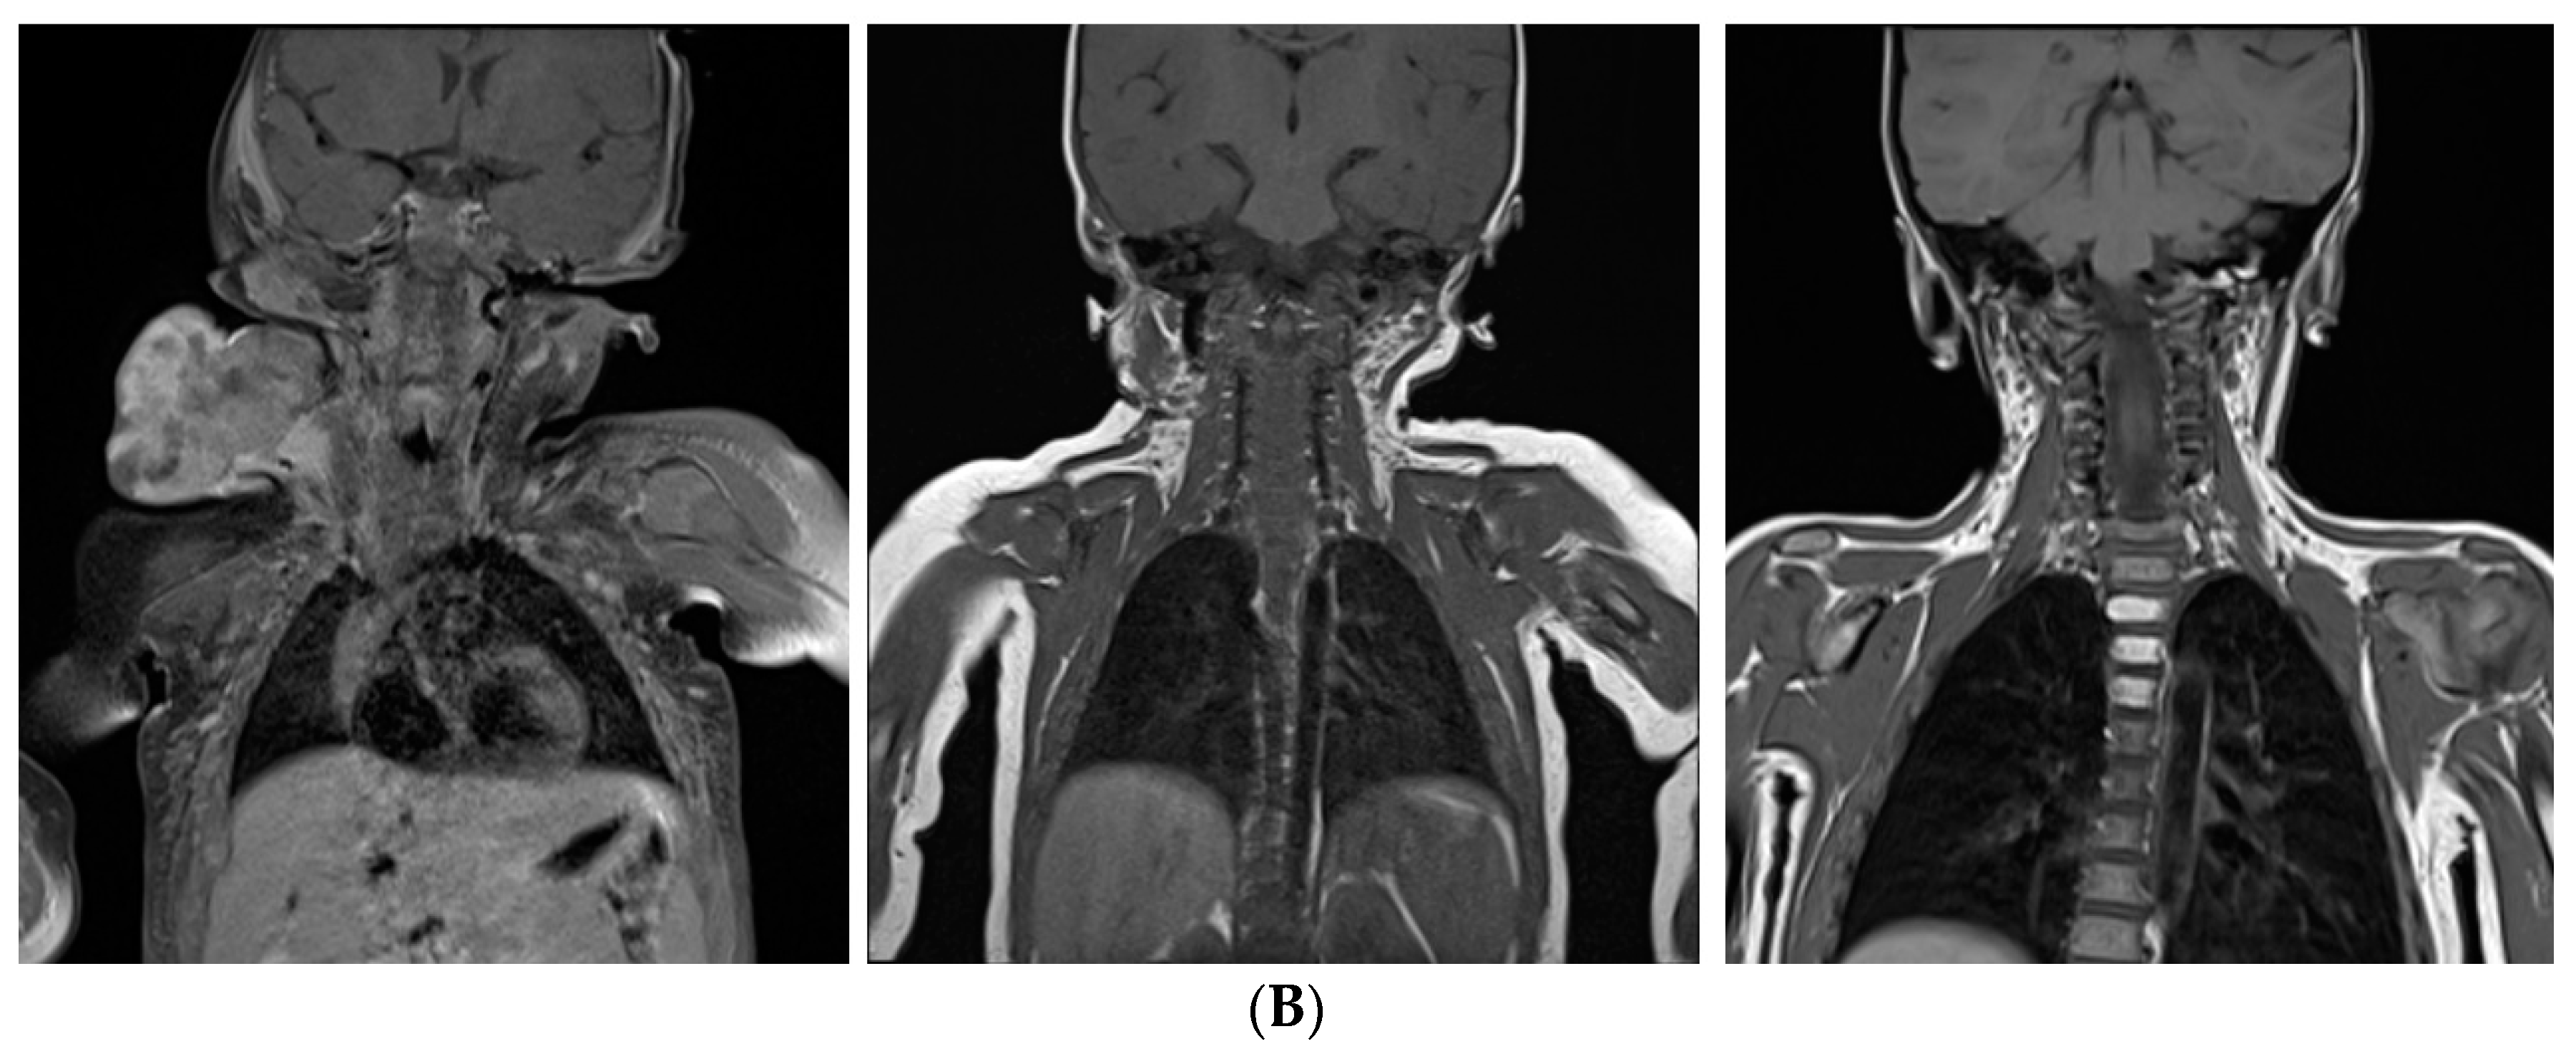

| Neck | 6 |